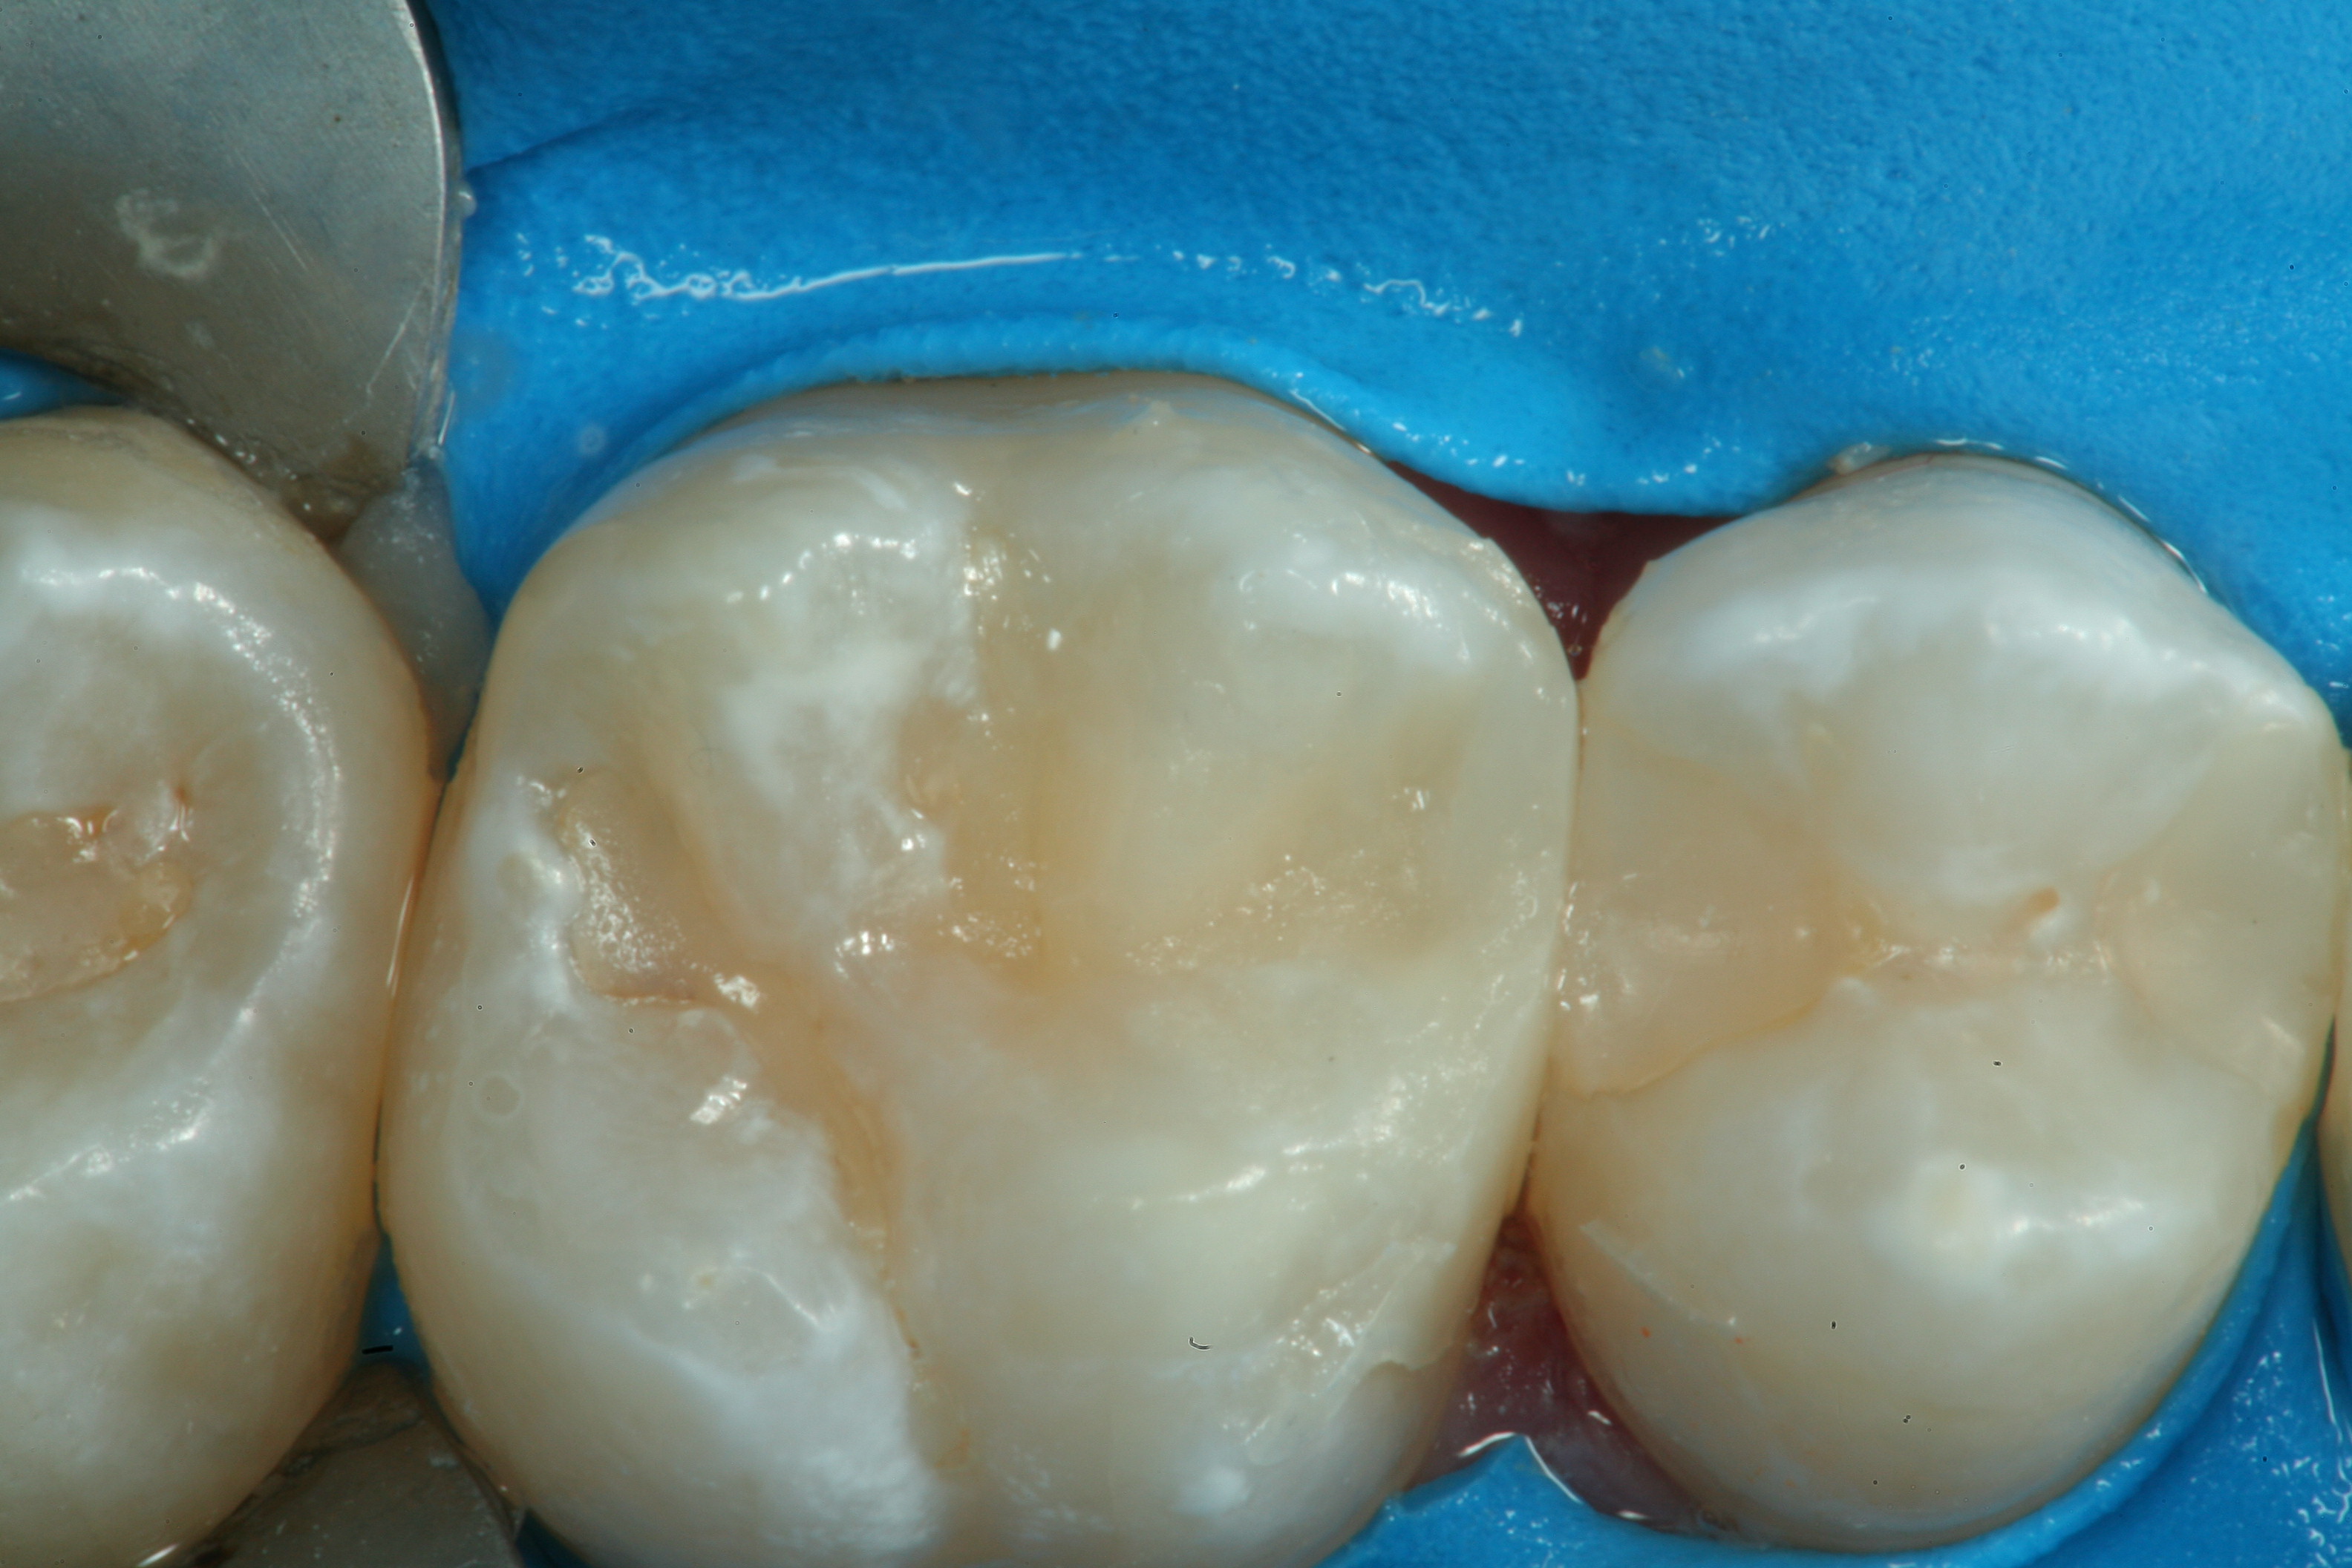

Fig 1. An occlusal view of teeth Nos. 29, 30, and 31 after micro-preparation with a Fissurotomy bur to remove decay diagnosed by quantitative light fluorescence (QLF).

Figure 1